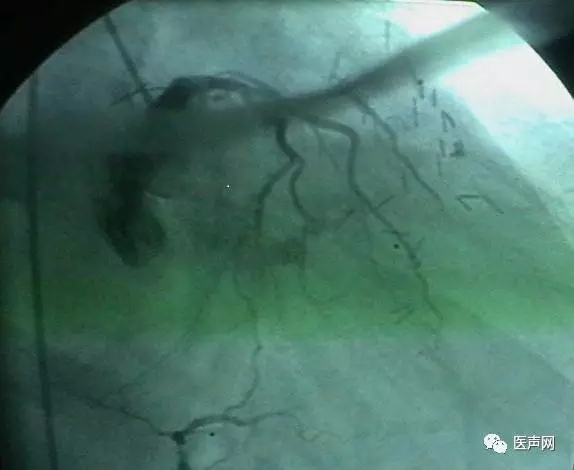

病例1: 冠脉搭桥术后,静脉桥CTO(CABG, VB-CTO)

箭头所示为第3个吻合点

(pre-PCI)

VB-对角支(jump)---LCX(jump)-PDA远端,第一个吻合以下完全阻断。

· 导引导管非常深置(Very very deep seating)(本例GC达CTO 第一吻合口前)(这是Dr. Lauer常用一招)

· 对侧造影

· 硬导丝(走得很远, 达PDA)

· 微导管,OTW 球囊.

当打通后,发生室速,电复律---出现无复流---室速---植入支架(TAXUS Liberte)

当导引导管非常深置(very very deep seating)时,你可以想象支持力有多大,永远不要忘记他做RCA-CTO时导引导管深插到RCA中段的例子。此病例实际上PDA未能开通,在6月28日 Dr. Lauer终于用类似方法打通了PDA。